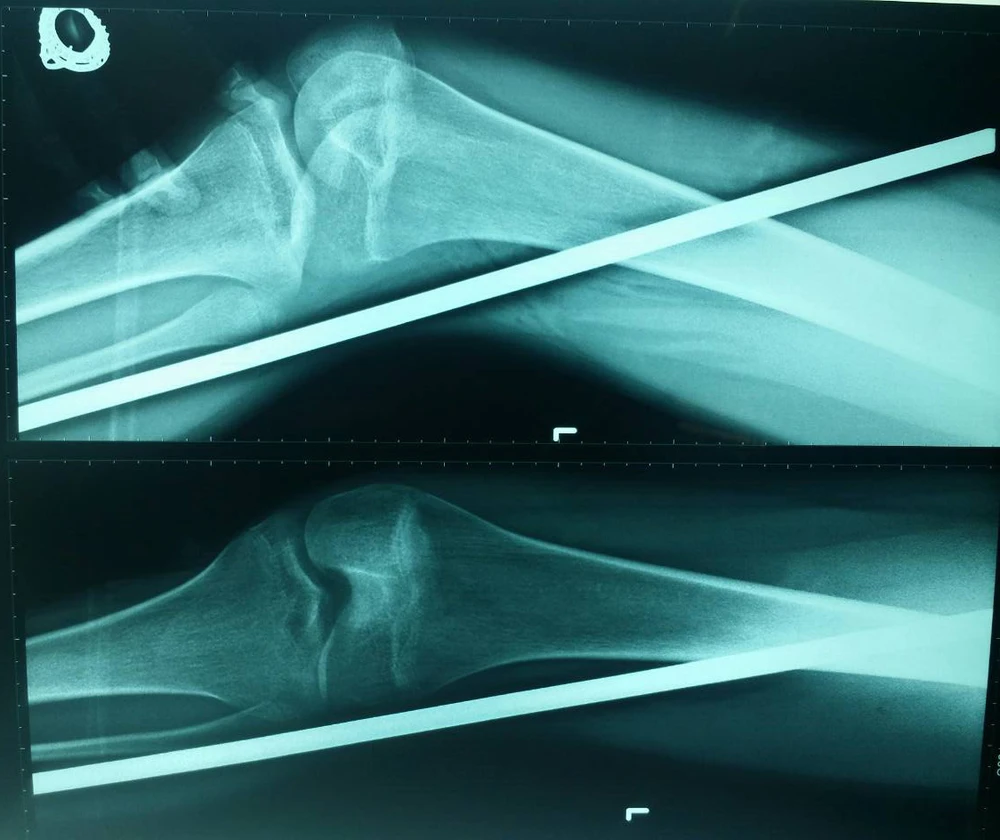

Kết quả chụp X-quang cho thấy cây sắt đâm xuyên từ đùi xuống gần mắt cá chân trái. Ảnh: ĐĂNG KHOA

Sáng cùng ngày, BV Chấn thương Chỉnh hình TP.HCM tiếp nhận bệnh nhân PTMP (15 tuổi, ở quận Bình Tân, TP.HCM) trong tình trạng bị cây sắt đường kính độ 12 mm, dài khoảng 30 cm đâm xuyên từ giữa đùi xuống gần mắt cá chân trái.

“Rất may thanh sắt chỉ xuyên qua phần mềm nên không ảnh hưởng tới xương bệnh nhân” - BS Khoa nói.